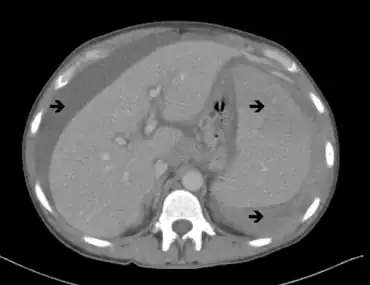

Additional tests such as computed tomography (CT or CAT) scan may be used to evaluate the chest, abdomen, and pelvis, particularly swelling of the lymph nodes, liver, and spleen. A skeletal survey can help distinguish between Waldenström macroglobulinemia and multiple myeloma.[50] Anemia occurs in about 80% of patients with Waldenström macroglobulinemia. A low white blood cell count, and low platelet count in the blood may be observed. A low level of neutrophils (a specific type of white blood cell) may also be found in some individuals with Waldenström macroglobulinemia.[49]